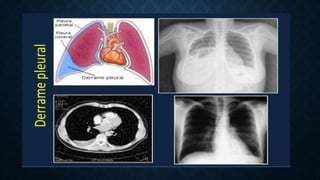

DEFINICIÓN

• En condiciones normales, el espacio pleural contiene

unos 15 mL de líquido pleural, que actúan como

lubricante.

• Equilibrio fisiológico entre su producción y absorción.

• Derrame pleural: acumulación patológica de

líquido.